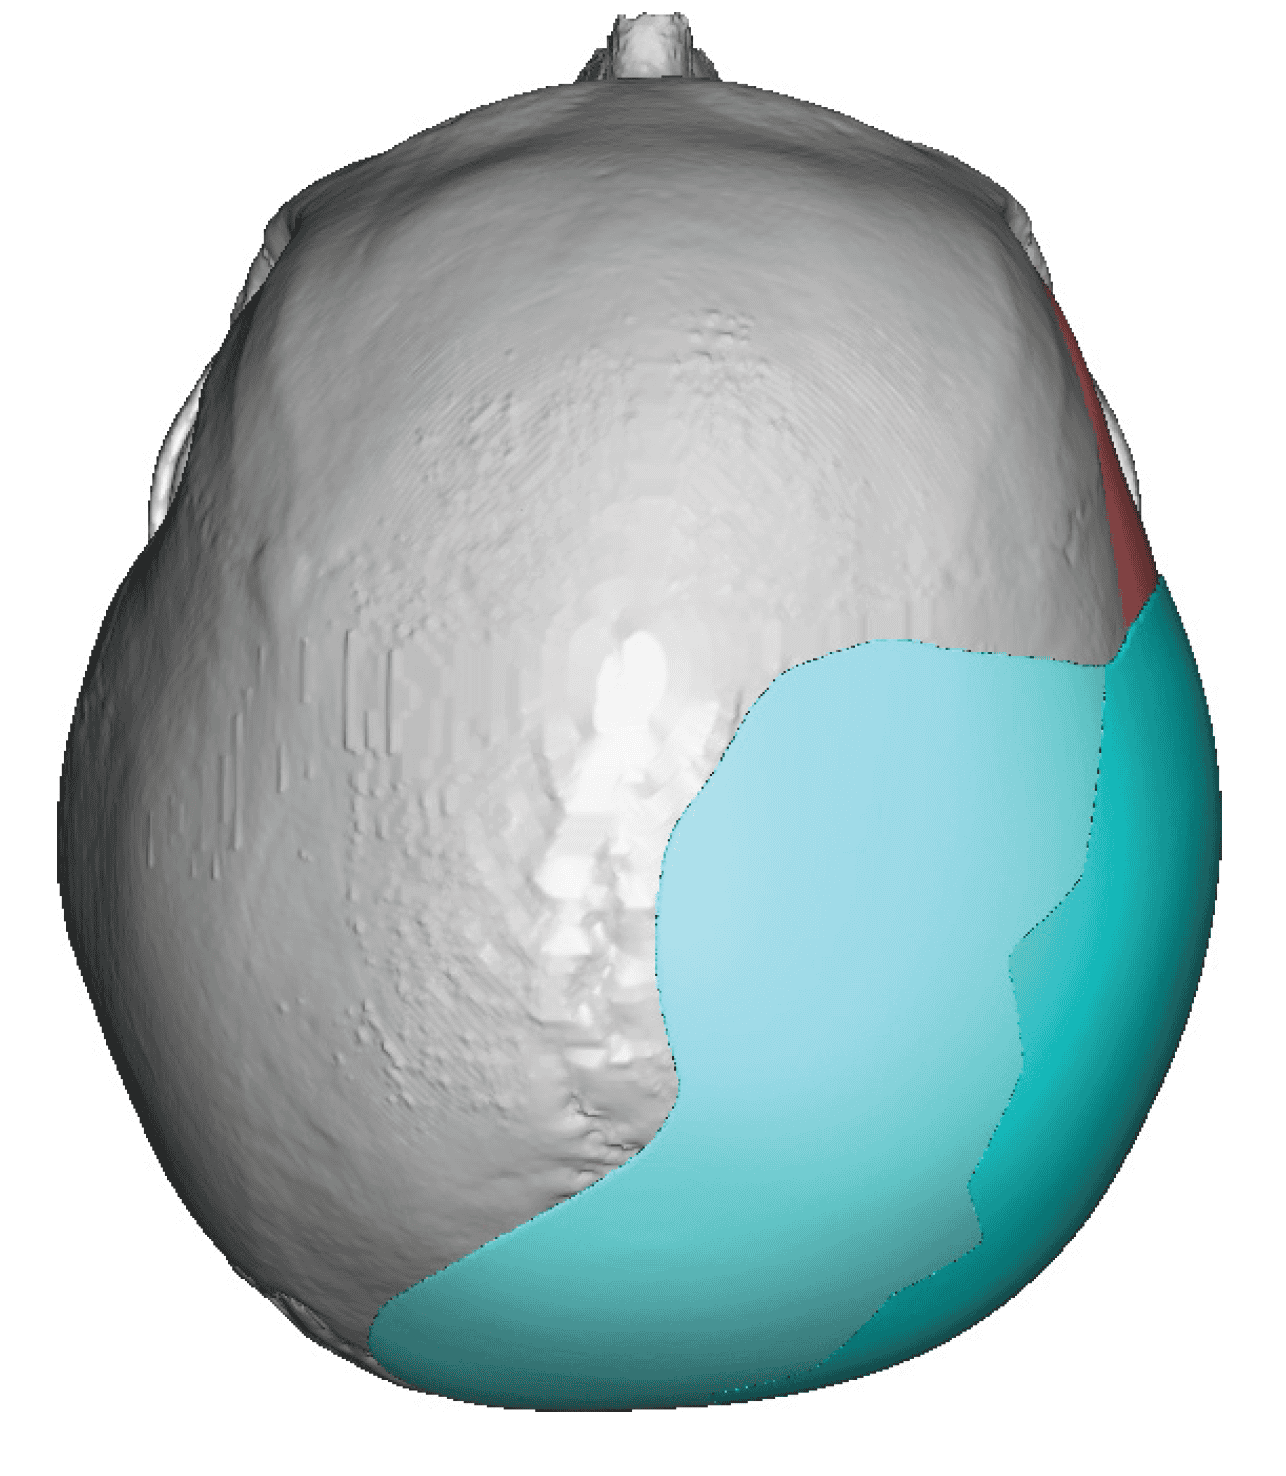

Patient 84

Desire for change of head shape from front view form an inverted V shape to a rounder and wider head shape.

Placement of custom extended forehead-temporal implants through incisions in the crease behind the ear. (he had a prior back of head skull implant which is green in the implant designs and which the head widening implants partially covered it)

Desire for change of head shape from front view form an inverted V shape to a rounder and wider head shape.

Placement of custom extended forehead-temporal implants through incisions in the crease behind the ear. (he had a prior back of head skull implant which is green in the implant designs and which the head widening implants partially covered it)